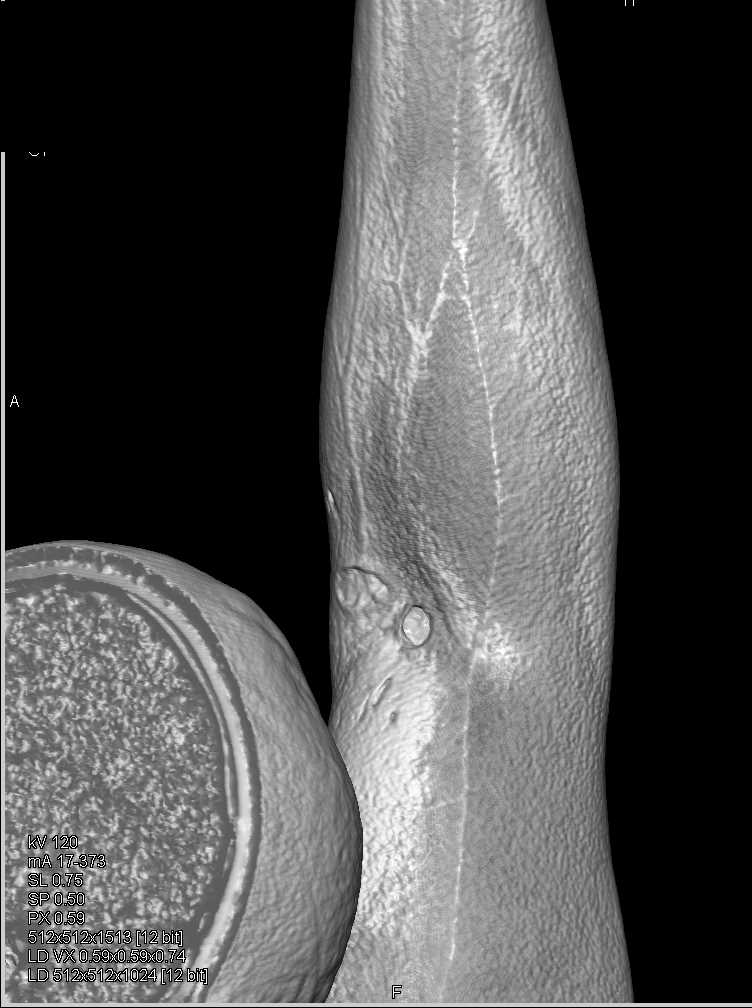

Soft Tissue Injury with Patent Vessels